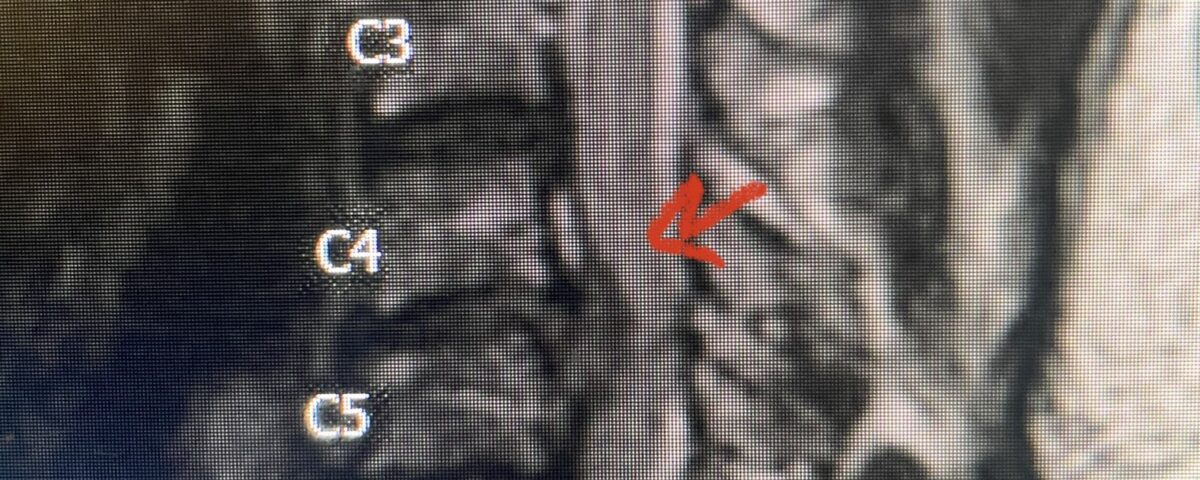

This 36-year-old female who had a long history of neck pain had a history on MRI of a C5-6 bulge. She recently after diving into a pool (not hitting her head on bottom) developed progressive problems with her arms. She had developed spontaneous shocks going down her arms and in the back of her neck. Spontaneous shocks going down the neck and spine is called a Lhermitte’s phenomenon and can occur with spinal cord compression and also with multiple sclerosis. On examination, the patient had long tract weakness of her arms, right greater than left. Her finger extensor weakness was profound on the right. MRI (Fig. 4) of the cervical spine revealed a massive C5-6-disc herniation causing significant cord compression right greater than left with subtle cord signal change. Because of the severe myelopathy, the patient was indicated for surgery. A C5-6 anterior cervical discectomy and fusion was performed (Fig. 5). The patient had a dramatic improvement of her strength in the recovery room.

Fig 4. Axial T2-weighted MRIs demonstrating large C5-6 herniated disc with spinal cord compression (red arrow)

Fig 4A. Axial T2 weighted MRIs demonstrating large C5-6 herniated disc with spinal cord compression (red-arrow)